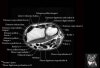

- Sagittal section

Sagittal T1 evaluates the tendons, bone marrow and relationships between the osseous structures.